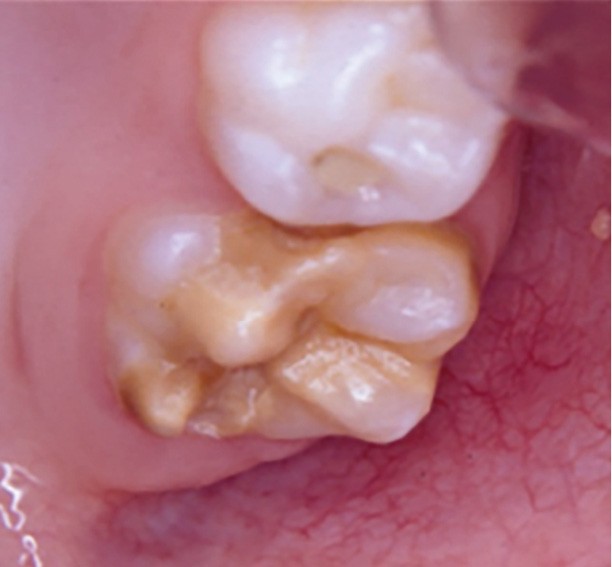

Cliniquement, les dents présentent des colorations blanches ou brunes opaques sur une partie ou sur toute la surface de la dent. Cette atteinte peut être légère (émail blanc, opaque), modérée (coloration jaune, brune, surface crayeuse et effondrement postéruptif de l’email) ou sévère (atteintes associées à des pertes de substances importantes) (fig. 1)

.